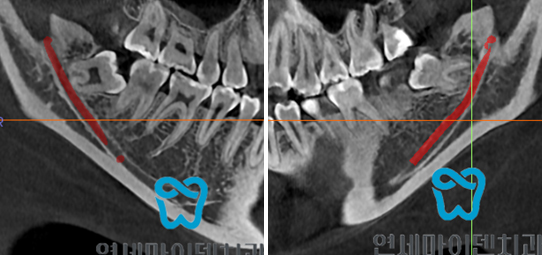

신경과 가까운 매복사랑니발치를 위해서는 3D - CT 정밀분석이 필요합니다.

반드시 3차원으로 분석을 해야 하죠.

앞으로 볼 땐 마치 매복사랑니가 신경과 닿아 있고 겹쳐져 있는 것으로 보이지만,,,,

3차원 다각도로 분석을 하면 매복사랑니가 신경과 닿아 있지 않을 수 있기 때문!

즉, 신경과 매우 가까운 매복사랑니발치를 안전하게 제대로 치료하기 위해서는

3차원 정밀 분석이 필수이며 3D-CT 분석이 가능한 치과를 가는게 좋습니다.